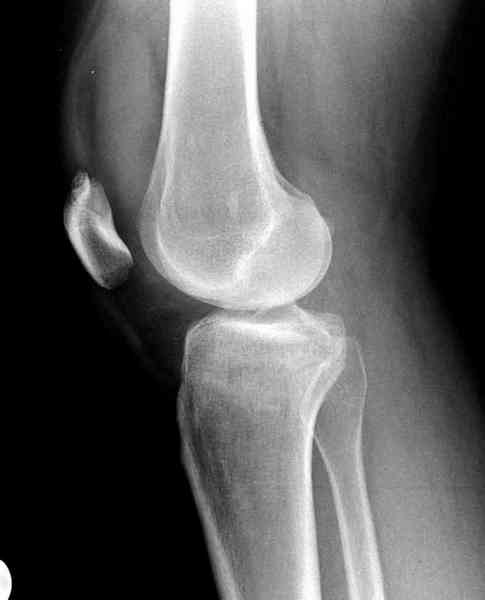

>"мыщелок левой голени будет прооперирован - репозиция, синтез пластиной с костной пластикой, при необходимости удаление повреждённой части мениска"

Для внутрисуставных переломов необходимо идеальное сопоставление, а такая задача без КТ срезов усложнится. Только КТ надо делать после дистракции сустава, иначе нельзя получить объективную информацию.

Около 60% переломов тибиал плато характеризуются мягкоткаными повреждениямм - разрывы суставной капсулы, связок и менисков. Мениск повреждается спереди со стороны перелома.

Тактику удаления мениска во время восстановления считаю ошибочной, наоборот, всеми путями надо его сохранить, потому что предупреждает от деформирующего артроза.

"Removal of a meniscus during the fracture surgery resulted in secondary degeneration in 74% of the cases. When a meniscus was intact or repaired, the proportion of degenerative cases was only 37%. Normal or slight valgus alignment of the tibial plateau with intact menisci protected best against secondary degeneration. On the other hand, medial or lateral tilt of the tibial plateau with a removed meniscus was followed by osteoarthritis in most cases. Honkonen SE., J Orthop Trauma. 1995"